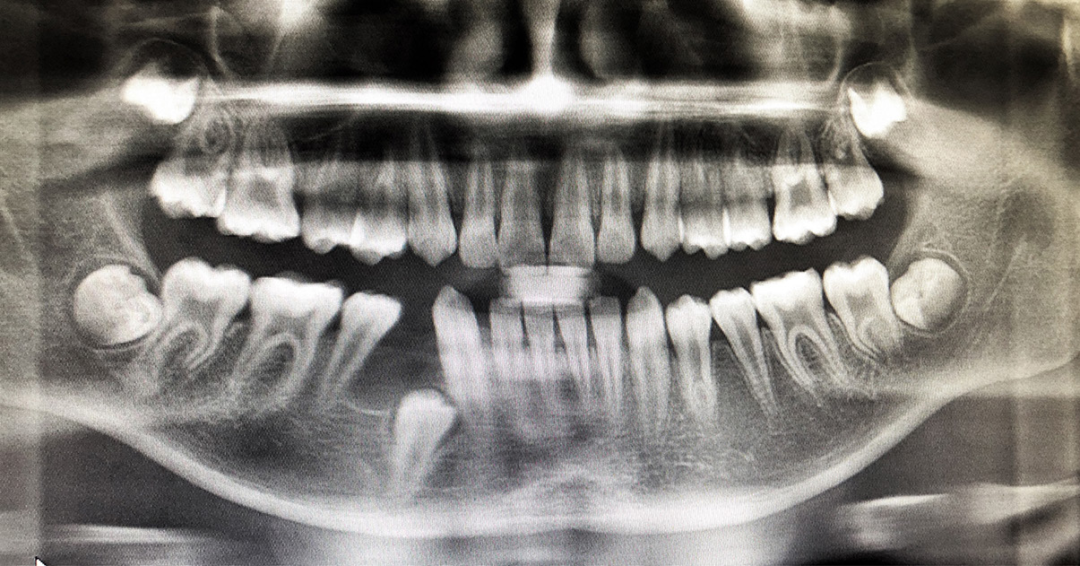

A:一般来讲,孩子十三岁的时候,这是能看到智齿的一个年纪,也就是说十三岁之前看不到,不一定都没有,但十三岁之后还没有智齿的胚芽,大概率不会出现了。我认为智齿不要着急拔,就想那么小的孩子,拔智齿得多疼啊,如果没有特别严重的发炎,或者快顶坏前牙那种程度,不要着急去拔。

那大家会觉得不拔智齿,会不会导致拥挤,前凸,仔细想想,我们这些错颌畸形,哪些是智齿导致的?我觉得智齿它不是决定性因素,所以家长不要着急去跟智齿较劲。

还有一个问题大家别忘了,就是我们的颌骨是在生长的,比如说上颌骨,上颌骨的最后边缘叫翼上颌裂。

上颌骨的后壁在生长发育高峰期之前,平均一年会长三个毫米的新骨;下颌骨在它的生长发育高峰期之前,下颌骨的后缘,升支的前缘每年也会长三个毫米的新骨。